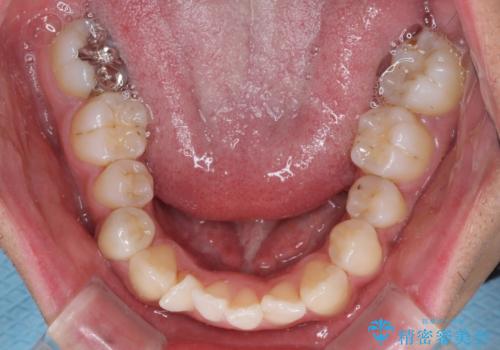

- 前歯のデコボコとクロスバイトを気にして来院された患者様です。

下顎の歯列弓に対して上顎歯列弓がやや小さく、側方の歯を中心にクロスバイトが見受けられました。

クロスバイトの改善は、インビザラインの場合歯髄壊死のリスクや咬み合わせが改善しきらないリスクがあるため、ワイヤー矯正をお勧めすることが多いですが、患者様の希望によりインビザラインにて矯正治療を行うこととしました。